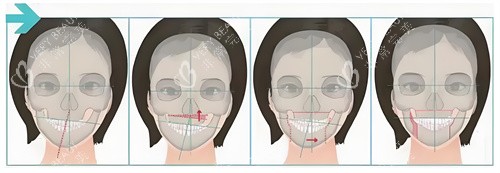

四、术后3个月:从“肿成猪头”到“自然侧颜”

“你这脸,肿得像馒头。”术后第3天,我妈举着冰袋给我敷脸,语气里带着心疼。我照着镜子,眼泪差点掉下来——下巴肿得像塞了个球,嘴唇麻得没知觉,连喝水都漏。

但医生早打过预防针:“前1周比较肿,2周后开始消,3个月基本自然。”我咬着牙忍:每天喝粥,不敢大笑,连睡觉都平躺,怕压到下巴。

第2周,肿胀消了一半,能勉强张嘴;***个月,下巴线条初现,侧脸终于不像“月亮”;第3个月,朋友约吃饭,盯着我说:“你这侧脸,顺眼多了。”我举着手机自拍,发现不用找角度,侧脸也能自然上镜。

现在,我敢大笑,敢露齿,敢发侧脸照——原来“正常”的感觉,这么爽。

术后3个月真的“自然”了吗?

——对别人来说,可能只是“下巴平了点”;对我来说,是“终于不用躲镜头的自由”,是“连笑都能自然”的底气。